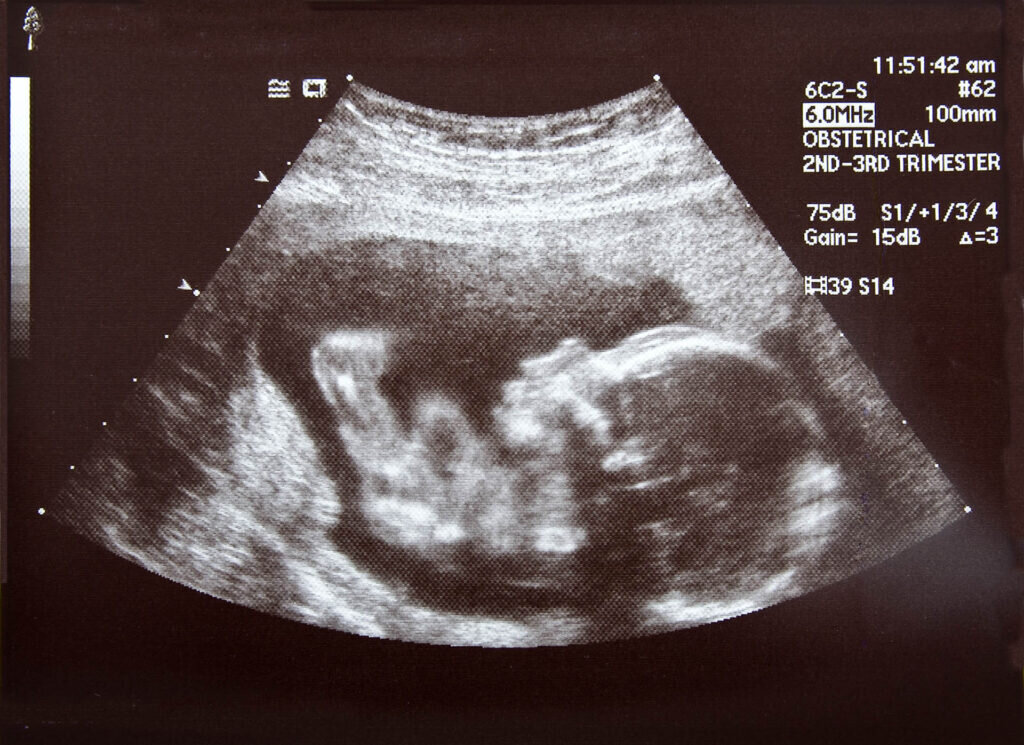

So, when Stuart saw influences seeking to draw young people in his church away from a pro-life position, he recognized the need to step into the gap. The result of his efforts was “Students in Action: Building Pro-Life Leaders,” a curriculum designed to be implemented in the local church that not only counters worldly influences; it goes further to help form young people as leaders who will influence the world for good by equipping them to be both advocates for life, and servants to the needs of families and children, especially women facing crisis pregnancies.